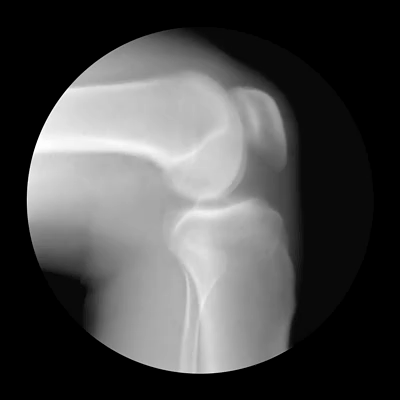

这种弹响多发于半月板,尤其是你的半月板扭伤过、磨损了的,这种响声可能代表半月板的再次损伤。

还有可能是由于关节的损伤致在运动时就会因关节组织的摩擦产生弹响,这也属于病理性弹响,这时候就千万不要运动了,赶紧去看医生。